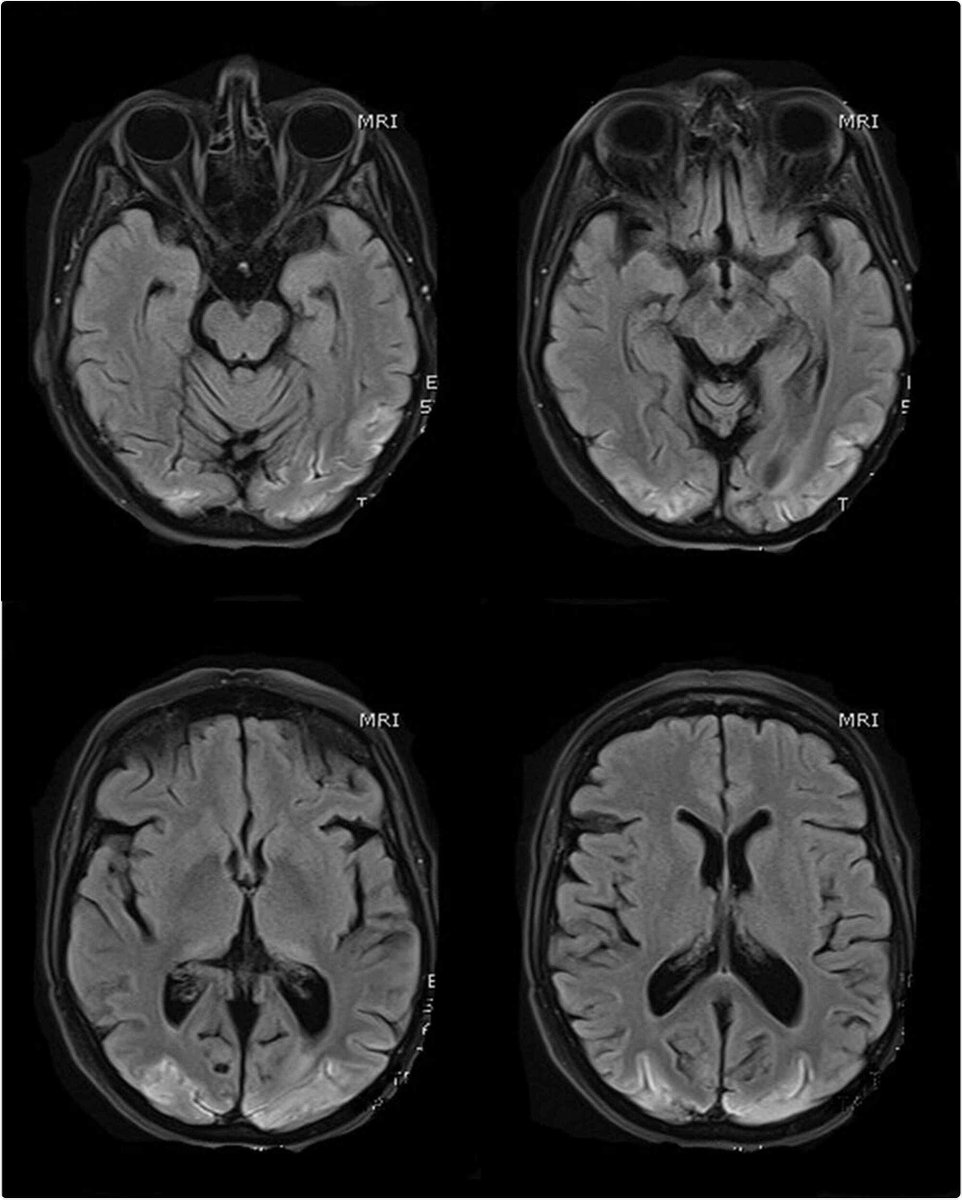

Complication of severe SARS-CoV-2 pneumonia results in persistent cortical blindness: Case report news-medical.net/news/20210131/… Cureus #Blood #Brain #Coronavirus #Encephalitis #Encephalopathy #Myelitis #Sepsi #COVID #SARSCoV2 #CorticalBlindness